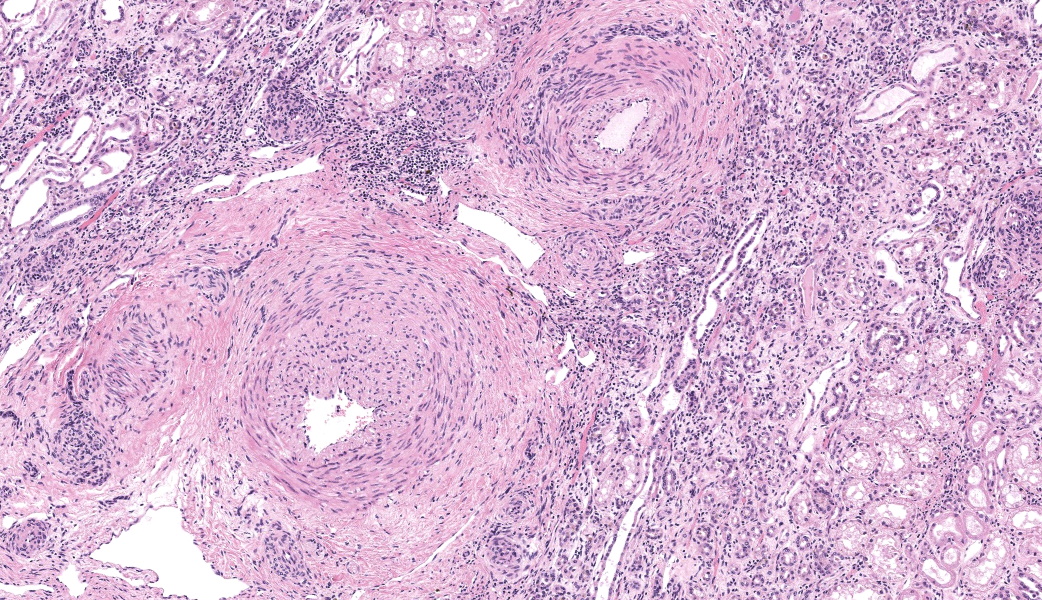

There are multiple sections of kidney that include cortex, medulla, and papilla. All of the glomeruli are affected to varying degrees of severity. The glomeruli are globally hypercellular, within both the endocapillary and mesangial compartments. Capillary walls are markedly thickened by eosinophilic matrix. There is frequent dilation of Bowman’s capsules and segmental collapsed glomerular tufts/ capillaries with expansion of mesangium with eosinophilic matrix (segmental sclerosis). Less than 25% of the glomeruli are globally sclerotic. Occasionally glomerular tufts are segmentally to globally effaced by eosinophilic mesangial matrix, and mesangial and intracapillary dark brown (hemosiderin) and yellow (hematoidin) pigment with scattered hemosiderin laden macrophages within Bowman’s space. There is infrequent segmental loss of podocytes with proliferation of eosinophilic matrix and cells that adhere the glomerular tuft to Bowman’s capsule (crescents). Several glomerular capillary loops are filled with fibrin thrombi.Over half of the tubules are characterized by attenuated epithelium, sloughed hypereosinophilic necrotic intraluminal epithelium, and/or piling of basophilic tubular epithelium (regeneration). Often tubules are dilated with eosinophilic proteinaceous material (hyaline casts), and contain intraluminal basophilic refractile material (mineralization). Infrequently, tubules are filled with degenerate neutrophils. There is a mild loss of tubules with expansion of the interstitium by fibrous matrix and aggregates of lymphocytes with fewer plasma cells. There are multiple arcuate arteries with an expanded tunica intima by increased numbers of smooth muscle cells and fibrous matrix, and/or thickened and hypercellular tunica medias (arteriosclerosis).

Thrombotic microangiopathy is characterized by endothelial cell damage that potentially produces thrombocytopenia and hyaline thrombi.3,5 Causes include genetic factors, malignant hypertension, pregnancy, drugs, transplantation, and infections.3 TMA is the lesion in Greyhounds with idiopathic cutaneous and renal glomerular vasculopathy, as well as the well-characterized hemolytic uremic syndrome in humans associated with Shiga or Shiga-like exotoxin of Escherichia coli O157:H7.3,4 In humans there are also several viruses associated with and thought to cause TMA.3,5 Therefore, in the present case, the superimposed lesion of TMA is likely related to CAEV infection and/or hypertension. The acute tubular necrosis in this case is likely related to ischemia possibly related to the vasculopathy as indicated by the arcuate arteriosclerosis and TMA lesions.

There was discourse on differentiating membranoproliferative from membranous glomerulonephritis based on histologic features, as some conference participants went one way or the other in their morphologic diagnoses. To summarize, membranoproliferative glomerulonephritis will have an increased number of nuclei within the glomerular tuft, mesangial cell proliferation, and often, the presence of recruited neutrophils. Membranous glomerulonephritis typically just has an increased amount (thickening) of basement membranes. One conference participant inquired on the histologic differences between synechiae and crescents in the glomerulus. Synechiae were described as the touching of the visceral layer of Bowman’s capsule to the parietal layer without fibrosis, whereas crescents have a fibrous component and demonstrate full adhesion of the glomerulus to the capsule. Conference participants did not think there was enough histologic evidence of thrombotic microangiopathy include it in the morphologic diagnosis in this particular case.